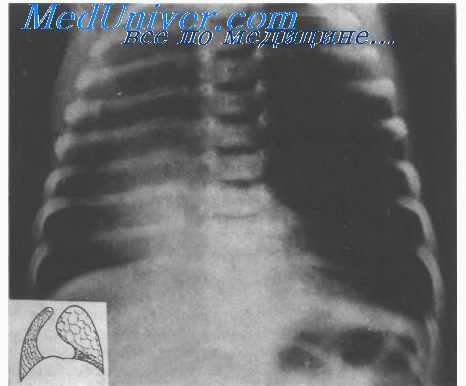

Острое вздутие паренхимы вызывает коллапс прилежащих отделов легкого н смешение органов средостения. В этой стадии процесса возможны диагностические ошибки. Повышенную прозрачность легкого принимают за напряженный пневмоторакс или напряженную солитар-ную кисту. Дифференцируют эти состояния главным образом рентгенологически. Некоторую помошь в дифференциальном диагнозе может оказать бронхологическое исследование. Однако при наличии „синдрома напряжения" это исследование опасно, так как введение в бронхи контрастной массы может усугубить дыхательную недостаточность.

Хронически текущая врожденная эмфизема имеет другую клиническую картину. Вздутый участок легкого, достигая определенного объема, не имеет тенденции к дальнейшему увеличению. Наступает адаптация к возникшим условиям вентиляции и гемодинамики и малом круге кровообращения. В покое одышка исчезает. Она возникает только при напряжении или не беспокоит вообще. При осмотре обращают на себя внимание некоторое выбухание грудной клетки на стороне порока и отставание ее при дыхании. Аускультативно над эмфизематозной частью легкого дыхание значительно ослаблено.

Рентгенологическая картина достаточно типична. На прямой рентгенограмме определяется повышенная прозрачность пораженной части легкого. Органы средостения смещены в здоровую сторону в большей пли меньшей степени, в зависимости от вздутия паренхимы. Легочный рисунок н области эмфиземы обеднен или отсутствует, в коллабированных отделах, наоборот, усилен. Бронхологическое исследование и контрастирование сосудов легких позволяют установить точный диагноз н определить степень нарушения функции пораженного легкого.